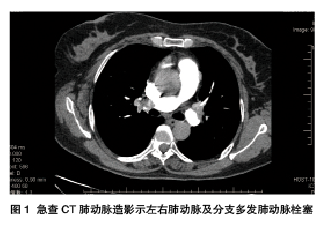

女性,55岁,因突发胸骨中下段疼痛,颈咽部紧缩感,气促,伴黑曚23 h,自服速效救心丸10粒无缓解,于2015年1月13日急诊,以急性冠脉综合征收入冠心病监护室(CCU)。患者1周前曾因外伤致左膝关节肿痛卧床1周,并在社区医院对肿胀的左下肢按摩治疗2次。患者自发病以来,有明显呼吸困难和气促,日常活动明显受限。13日急查CT肺动脉造影示左右肺动脉及分支多发肺动脉栓塞(图1),遂转入RICU。急查双下肢超声示左侧髂静脉血栓形成,左侧胫后静脉及双侧小腿肌间静脉血栓。诊断急性肺栓塞(中高危)和深静脉血栓形成,予以溶栓治疗。21日心脏超声示右心比例稍大,右肺动脉增宽,肺动脉收缩压升高,TI法估测肺动脉收缩压约42 mmHg。30日出院并继续口服华法林抗凝治疗。